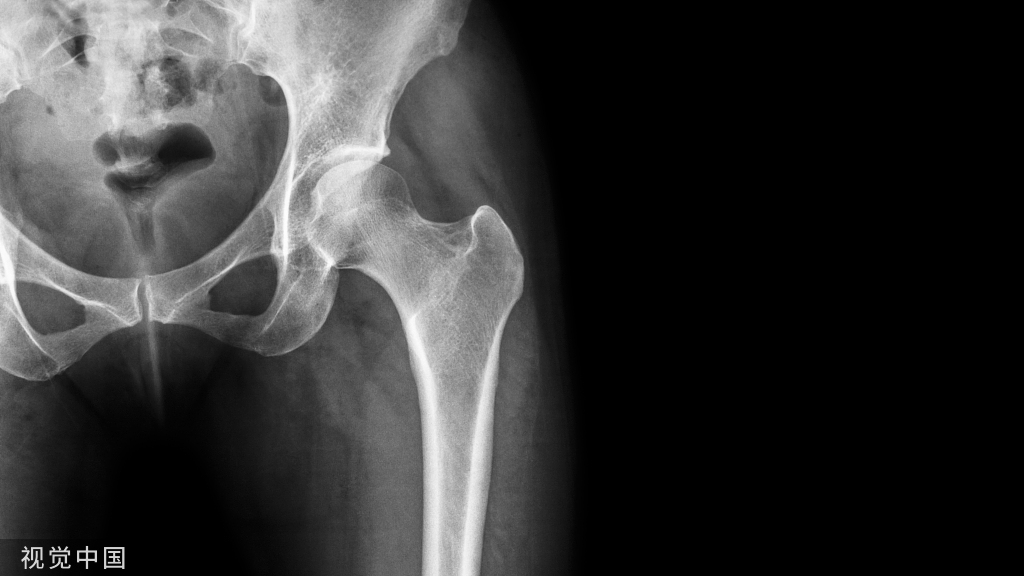

在老年人所有骨折中,髋部骨折是最严重的类型。髋部骨折因其预后差、并发症多、死亡率高的特点,在老年人中被认为是“生命中的最后一次骨折”。随着年龄的增长,老年人身体机能、协调性、反应能力下降,髋关节周围肌肉力量下降,同时体内钙流失严重,骨密度下降。当髋关节受到外力轻微撞击时,就会发生骨折。